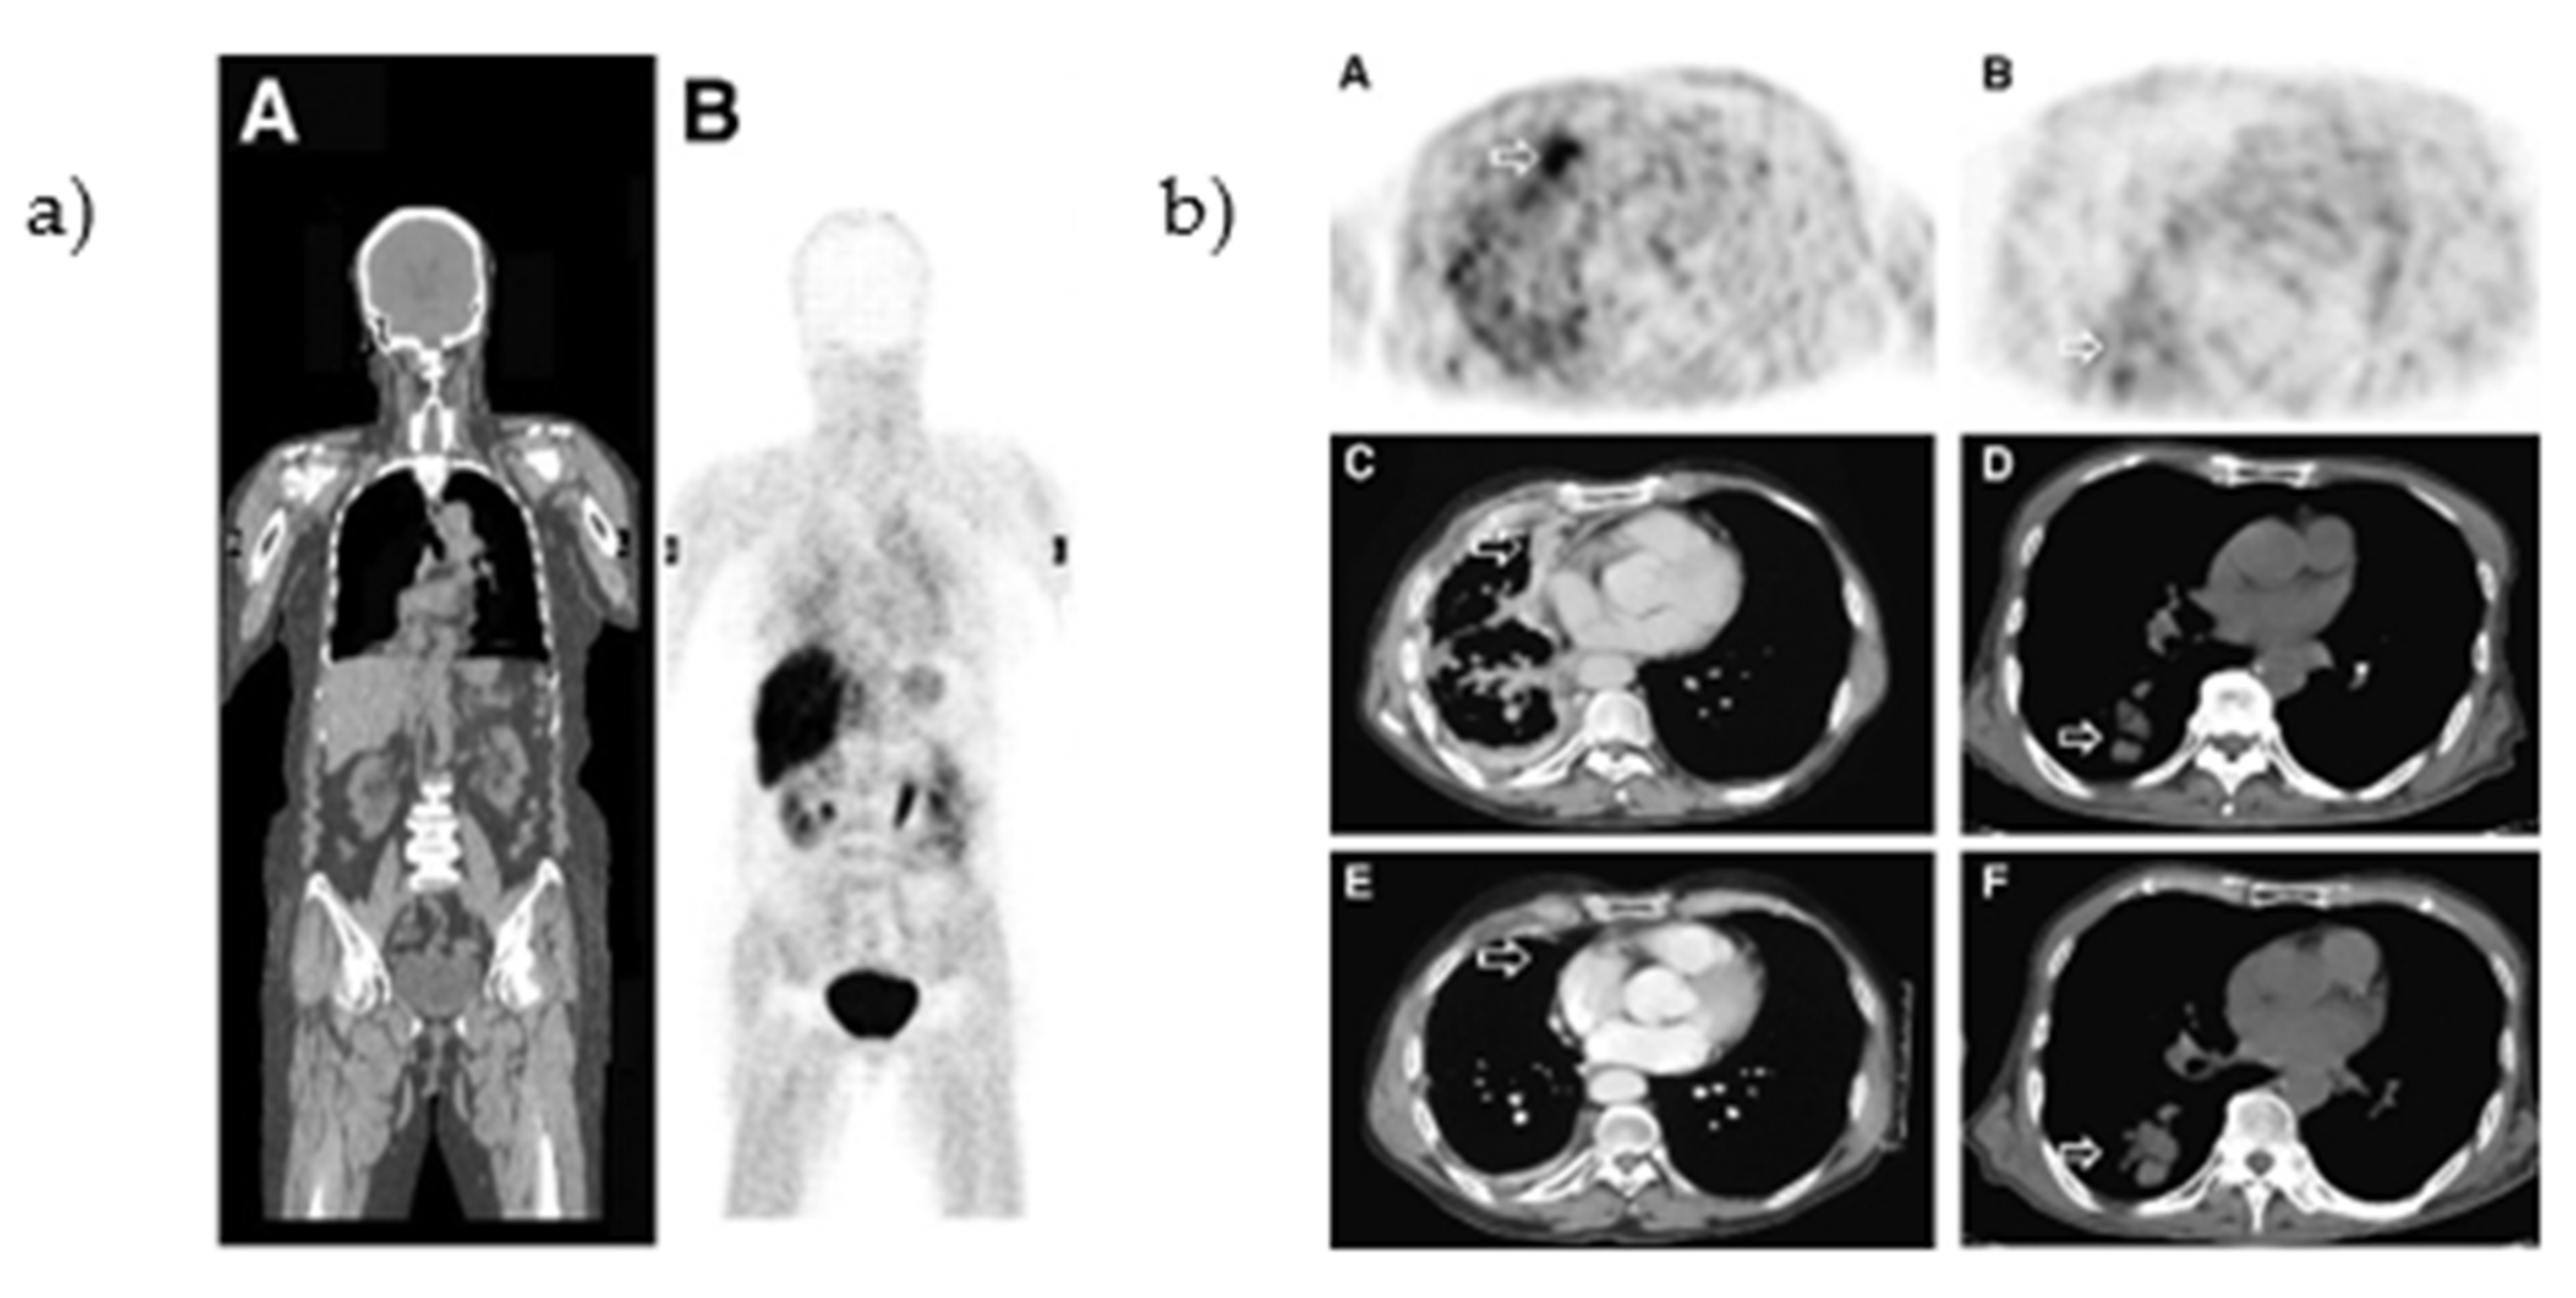

The biodistribution of [O-methyl-11C]PD153035 was evaluated in healthy human volunteers. At 60 min post-injection, the highest uptake was observed in organs connected to the renal and hepatobiliary system (bladder, gallbladder, kidneys, small intestine, and liver, Figure 4a) [43,44]. In a pilot study, the uptake of [O-methyl-11C]PD153035 was correlated to the EGFR expression levels (determined by immunohistochemistry and western blot) in gliomas. The majority of the glioblastomas could be visualized with PET with a SUVmax-to-white-matter ratio of 1.77 ± 0.41 [45]. In addition, Meng et al., correlated the tumor uptake to the efficacy of erlotinib therapy (mutational status of the tumors was not established). A baseline PET/CT scan was performed in 21 patients with adenocarcinoma or squamous cell carcinoma before the initiation of erlotinib treatment (Figure 4b). One to two weeks after the initiation of treatment, a second PET/CT scan was performed. The SUVmax at baseline and the second scan correlated with the overall survival (OS) and progression-free survival (PFS). In contrast, a third scan performed six weeks after treatment initiation did not correlate to either prognostic indicator [46].

Figure 4.

(a) [O-methyl-11C]PD153035 whole-body distribution 30–40 min after injection in a healthy volunteer. Adapted from [44], with permission from SNMMI. (b) Baseline [O-methyl-11C]PD153035 PET in (A) an adenocarcinoma patient and (B) a squamous cell carcinoma patient, with corresponding CT before treatment (C,D) and 6 weeks after treatment (E,F). Adapted from [46], with permission from SNMMI.